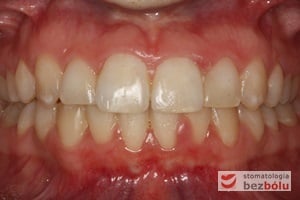

Pacjentka lat 22 zgłosiła się do naszej placówki celem podjęcia leczenia ortodontycznego. Głównym oczekiwaniem pacjentki była poprawa estetyki uśmiechu oraz brak ekstrakcji zębów na drodze do jej uzyskania. Ze względu na liczne stłoczenia zębów w górnym i dolnym łuku, dość duży materiał zębowy w porównaniu z bazą kostną, a także zgryz przewieszony boczny prawostronny po dokładnej analizie cefalometrycznej oraz analizie modeli diagnostycznych zastosowano leczenie bezekstrakcyjne z wykorzystaniem strippingu jako alternatywy dla usuwania zębów, mającego na celu uzyskanie miejsca w łuku na uszeregowanie zębów. Po fazie aktywnego leczenia trwającego 18 miesięcy zastosowano leczenie retencyjne w postaci szyny retencyjnej w łuku górnym oraz retainera stałego w łuku zębowym dolnym klejonego od kła do kła.